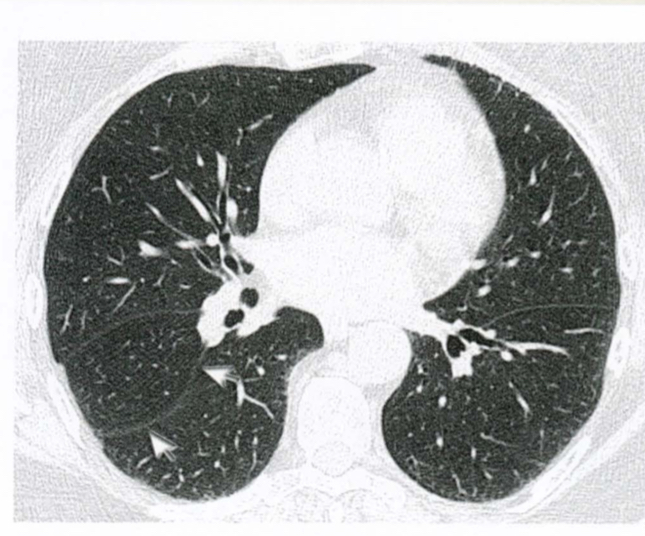

Quais são as estruturas apontadas?